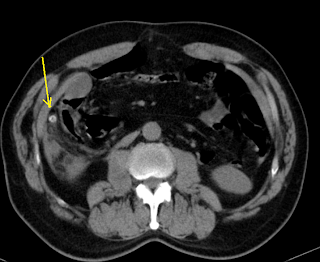

Specific CT scan findings of appendicitis include enlargement of the appendix ( more than 6 mm in the outer diameter), enhancement of the appendiceal wall, lack of opacification in an enlarged appendix, fat stranding in the periappendiceal region, and the presence of an appendicolith within the appendix.